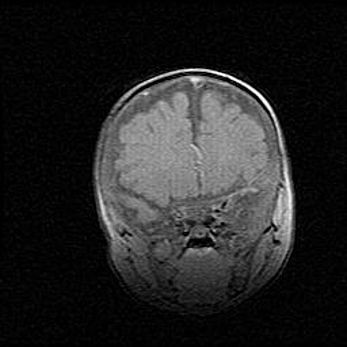

Открытая гидроцефалия.

Возраст: 9 месяцев 12 дней

Вес: 6800 г

Пол: мужской

Окружность головы: 41,5 см

Срок гестации: 28 недель

Гидроцефалия головного мозга у новорожденных имеет характерный признак: опережающий рост окружности головы приводит к визуально хорошо определяемой гидроцефальной форме сильно увеличенного в объёме черепа. Детские неврологи определяют следующие симптомы гидроцефалии у грудничков: выбухающий напряжённый родничок, частое запрокидывание головы, смещение глазных яблок к низу.